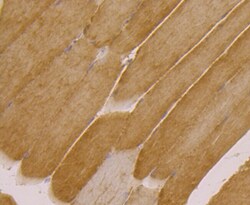

Immunohistochemistry

MA5-34909 IHC